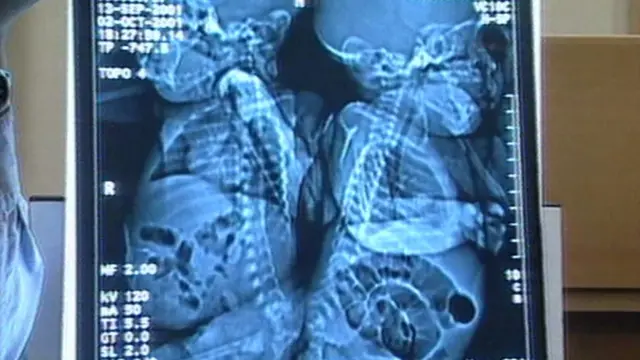

U decembru 2001. u Birmingamu je izvršen opasan operativni zahvat kako bi se razdvojili tromesečne sijamske bliznakinje, Sančija i Eman Mauvat.

Na koncu naporne šesnaestočastovne operacije, dve male devojčice bile su razdvojene. Provele su prva tri meseca života povezane kičmom.

Bio je to izuzetan dan u Birmingemskoj dečjoj bolnici - prvi put je takva operacija izvedena u Ujedinjenom Kraljevstvu, a bila je tek treća u svetu.

Operacija neophodna za razdvajanje kičmenih stubova Sančije i Eman, koji su bili spojeni u korenu, nikad pre nije bila izvedena u Ujedinjenom Kraljevstvu.

Lekarski tim predvođen Tonijem Hoklijem razdelio je kičmeni stub i razdvojio neke osnovne organe, među kojima su i bešike.

Opisujući kasnije proceduru, Hokli je izjavio za Gardijan: „Njih dve su se spojile u jedno. A došlo je i do izvesne rotacije. Morali smo da sečemo tako da svaka devojčica dobije svoj kičmeni stub i da napravimo kanal kako bismo ga pokrili.

„Tehnika sečenja je uobičajena, ali potrebno je znati gde treba da se pravi rez. Pomagali su nam stimulatori nerava."

Nakon što su im kičme razdvojene, dečji hirurg Piter Gornal i jedan od vodećih svetskih stručnjaka za sijamske blizance Luis Spic, iz dečje bolnice Grejt Ormond strit, pažljivo su razdvojili neke organe devojčica, koji su bili celi, ali spojeni.